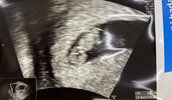

Ja dziś byłam na usg, jest serduszko ❤️

• 134C3A5B-DECC-4995-852C-4312BA835FDE.jpeg